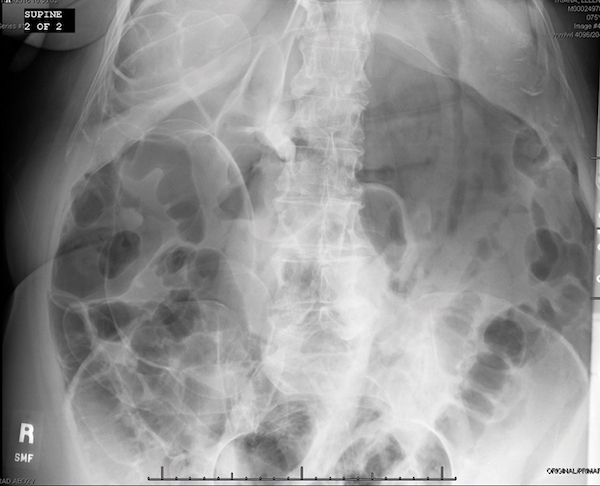

A 56-year-old woman presents for screening colonoscopy. She has had 2 previous attempts at colonoscopy that were unable to be completed due to tortuosity of the colon. Those procedures were terminated in the transverse colon. Today, with the help of pressure, the scope is passed with ease to the cecum. She has three 1-2-mm sessile polyps resected with a cold biopsy forceps. Following the procedure, the patient feels well and is discharged. She calls you about 2 hours later stating that she is having excruciating abdominal pains. You return her call and advise her to go to the emergency department. In the ED, the abdominal x-ray reveals the following [FIGURE]. What segment of the colon is most likely involved with this complication?

A. Cecum

B. Ascending colon

C. Transverse colon

D. Descending colon

E. Sigmoid colon

The sigmoid colon has been shown to be the most common location for colonic perforation in multiple studies. The largest study that looked at this was a 16-year study with 30,366 colonoscopies. There were 35 perforations (0.12%) or 1 in 1,000. The most common location for perforation was the sigmoid colon with 26 perforations (74%).